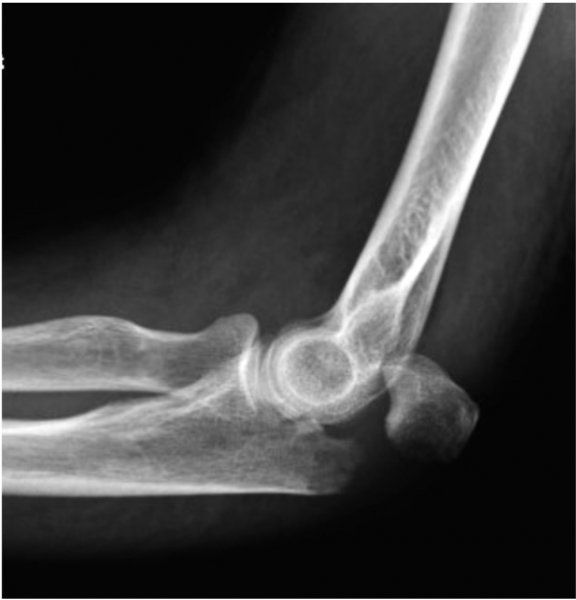

Fractures of the olecranon may be suspected from the mechanism of injury resulting in pain, deformity and bruising over the outer aspect of the elbow. The diagnosis is confirmed on X-rays of the elbow. In some instances a CT scan may be arranged to study the fracture in greater detail and help plan surgical treatmen